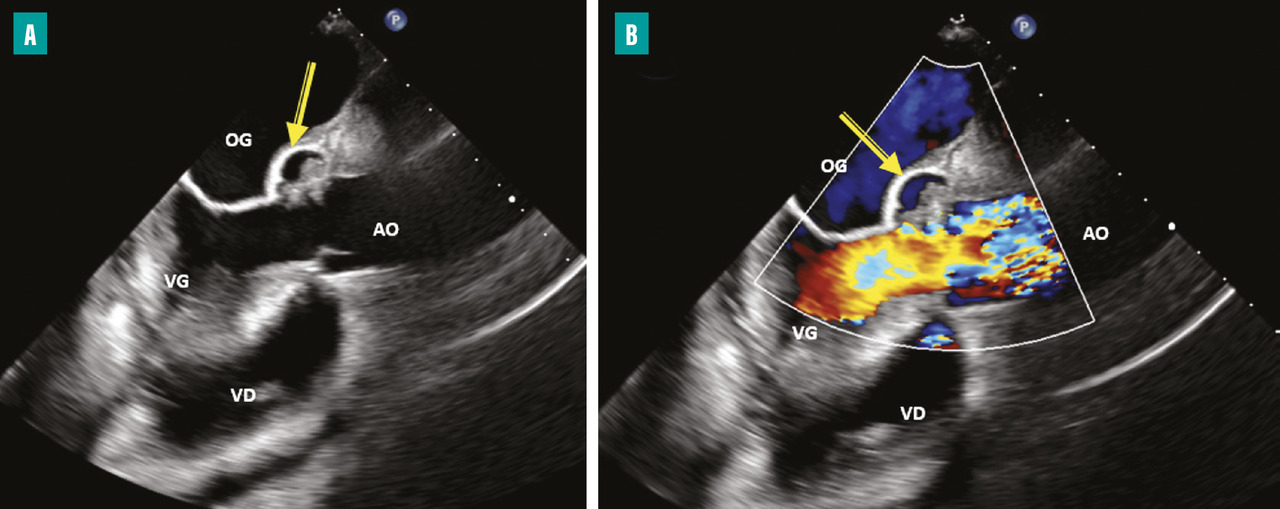

Les accidents emboliques représentent la deuxième cause de mortalité de l’EI. Leur incidence est estimée entre 10 et 50 %.6,7 Ils sont en rapport avec la fragmentation et la migration d’une partie d’une végétation dans la circulation artérielle pour les EI du cœur gauche et dans la circulation pulmonaire pour les EI du cœur droit. Ils sont dominés par les accidents neurologiques, suivis des embolies spléniques, rénales et pulmonaires. Le risque embolique est maximal au début du traitement antibiotique, puis diminue progressivement dans les deux premières semaines de traitement pour devenir minime ensuite.8,9 Dans environ 20 % des cas, l’embolie est cliniquement silencieuse et mise en évidence uniquement sur l’imagerie. Les facteurs prédictifs d’un haut risque embolique dans l’EI sont : la taille de la végétation (haut risque si supérieur à 10-15 mm [fig. 1 ]), sa mobilité et sa localisation sur la valve mitrale, l’EI à Staphylococcus aureus et la non-réduction de la taille des végétations sous traitement antibiotique.6

Les indications de la chirurgie en prévention des accidents emboliques sont précisées dans les recommandations européennes de 2023 :4

– en présence d’une végétation de plus de 10 mm sur valve native ou sur prothèse valvulaire ayant embolisé malgré une antibiothérapie adaptée (recommandation de classe IB) ;

– en l’absence d’embolisation mais avec une végétation de plus 10 mm associée à une autre indication chirurgicale (insuffisance cardiaque, par exemple) [recommandation de classe IC] ;

– à discuter en présence d’une végétation de plus de 10 mm sans dysfonction valvulaire sévère ni accident embolique et d’un faible risque opératoire (recommandation de classe IIbB).